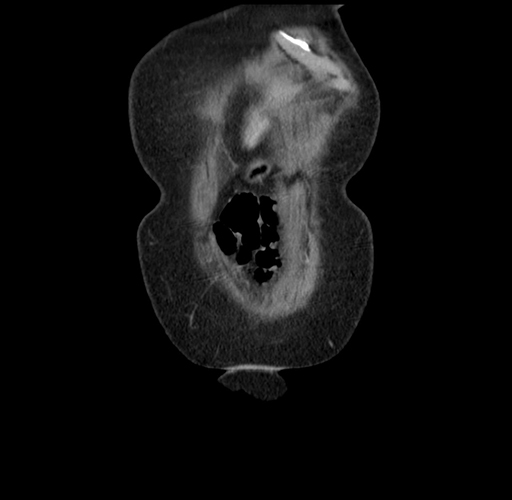

Pre-Chemo: Axial Venous

Pre-Chemo: Coronal Venous